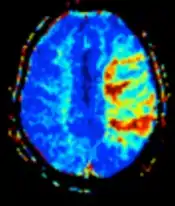

| Perfusion weighted (PWI) | Dynamic susceptibility contrast | DSC | Measures changes over time in susceptibility-induced signal loss due to gadolinium contrast injection.[72] |

|

![]() |